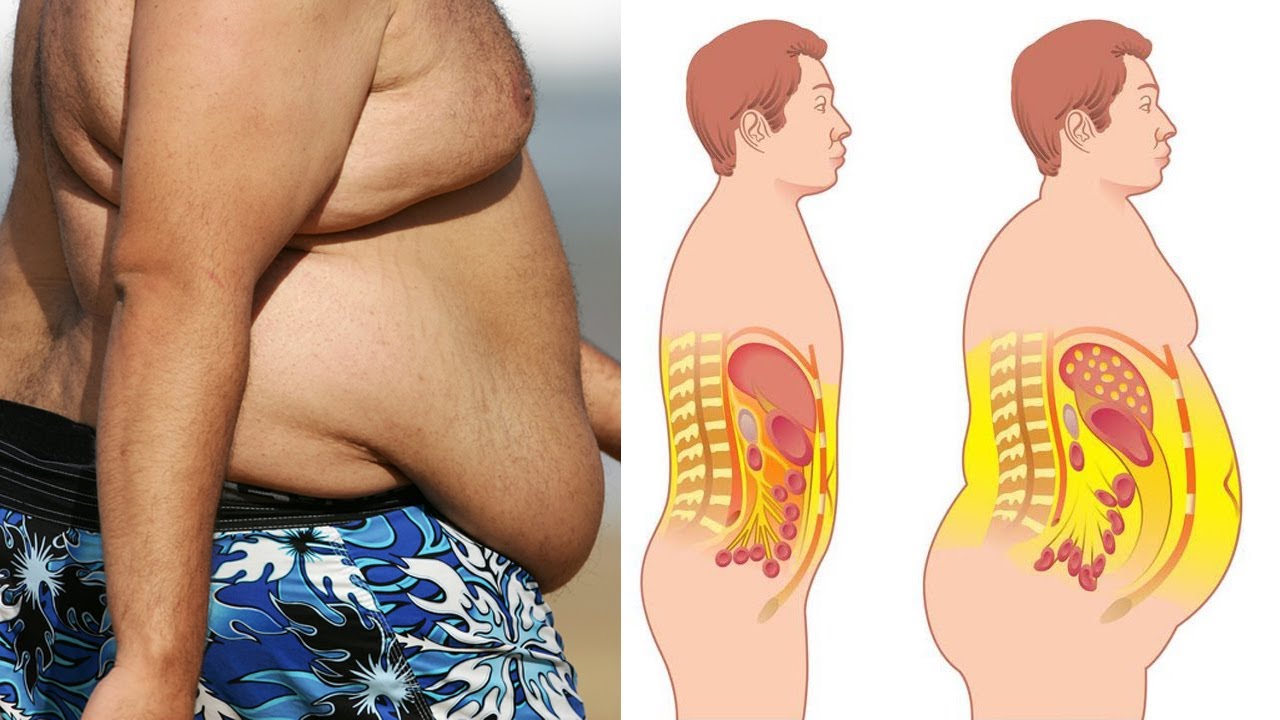

Постепенно вводите умеренную физическую активность в свою жизнь. Регулярные занятия спортом помогут ускорить обмен веществ и способствуют снижению жировой ткани в печени.

Избегайте переедания и контролируйте свой вес. Жирное скопление в организме может наносить вред печени и ухудшать ее функции.